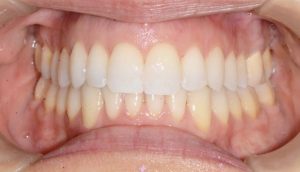

אחת התופעות עליהן מתלוננים רוב המתרפאים ממוצא אירופאי היא בליטה של השיניים הקדמיות העליונות.

במקרים בהם ישנה צפיפות גדולה מאוד של שיניים ו /או בליטה גדולה שלהן כלל הטיה אלכסונית שגורמת לליקוי אסתטי יפנה האורתודונט את המתרפא/ה לעקירות שיניים קבועות.